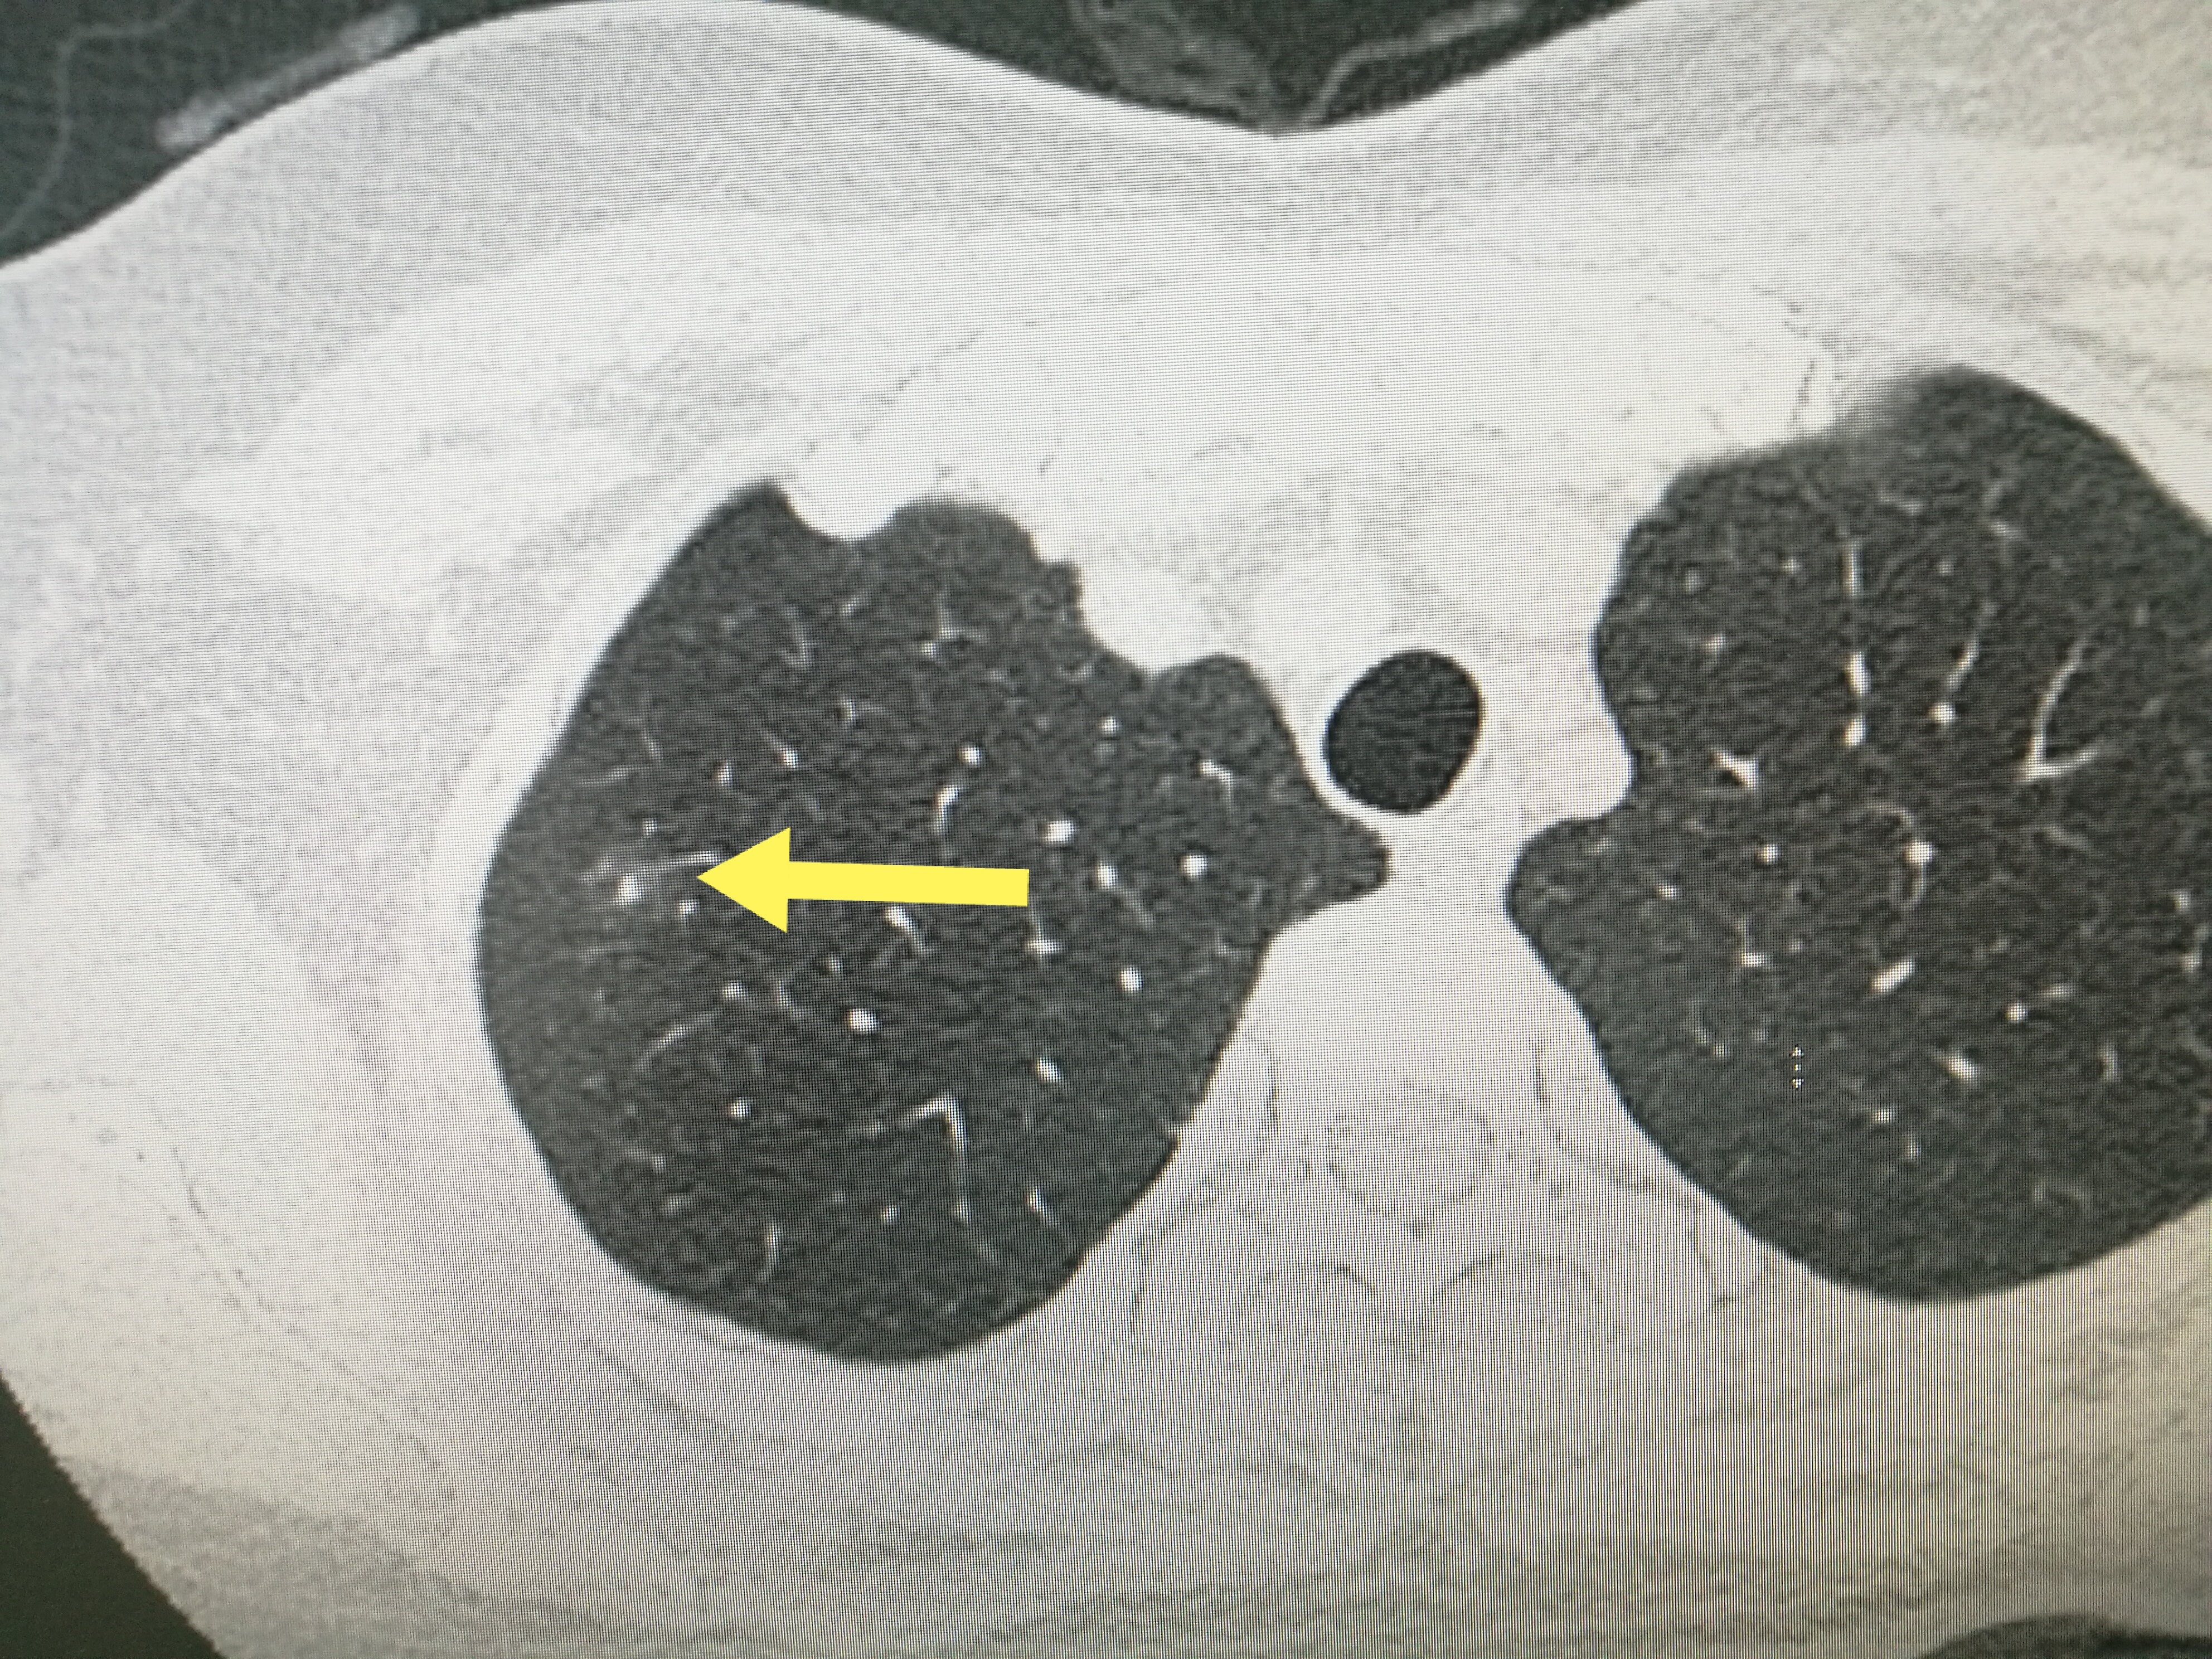

肺囊肿是指肺部半径大于或等于3公分的类方形或不规形病变,影像学表现为密度增高的阴影,可单发或多发,边界清晰或不清晰的病变。为了对肺囊肿病人进行精准管理,逐步将肺囊肿中半径大于5毫米者定义为微小病变,半径为5~10毫米者定义为总结节。不同密度的肺囊肿,其恶性机率不同,根据病变密度将肺囊肿分为3类:实性病变、部分实性病变和磨玻璃密度囊肿。其中肺结节最怕三种运动较真,部份实性病变的恶性机率最高,其他依次为磨玻璃密度囊肿和实性病变。部份实性病变是指其内既包含磨玻璃密度又包含实性软组织密度的结节,密度不均匀。磨玻璃密度囊肿是指肺部模糊的病变影,病变密度较周围肺实质略降低,但其内神经及支食道的轮廓尚可见。实性病变是指其内全部是实性软组织密度的病变,密度较均匀,其内神经及支食道影像被遮掩。

临床上主要通过CT影像从增生的外型结构和内部特点两个视角初步判定肺囊肿的良恶性,包括囊肿大小(增生越大,恶性机率越大)、边缘(分叶、毛刺和或骨膜凸起征,恶性机率大)、内部结构特点(囊肿内支喉部及心脏特征:支喉管被包埋且伴局部管壁增厚,或包埋的支食道腺体不规则,或有迂曲增粗神经长入,则恶性或许性大),以及随访中增生的动态变化。肺囊肿在随访中有以下变化时,多考虑为恶性:①直径减小,倍增时间符合病变生长规律;②病灶稳定或减小,并出现实性成份;③病灶缩小,但出现实性成份或其中实性成份提高;④血管生成符合恶性肺囊肿规律;⑤出现分叶、毛刺和(或)腹膜凸起征等。其实,肺囊肿的良恶性还须要结合病人病程、肿瘤的高危诱因、肿瘤指标,以及相关基因烷基化等诱因进行综合判定。若果还不能断定,对于实性成份在1公分以上的病变还可以选择PET-CT、增强CT进行检测来帮助辨别。假如想要精确晓得病变的良恶性,只有通过放疗或CT下肺囊肿穿刺等方式获取组织做病理检测就能明晰。急诊上发觉不少病人同学们常会按照自己从互联网以及抖音、小红书等自媒体平台上见到的知识来辨别病变的良恶性。在此还要告诫你们的是,尽管恶性病变在CT影像上有上述所说的一些特性点,但并不是这么绝对,这些恶性病变并不典型,这些经验丰富的学者还有看走眼的时侯,所以断定肺囊肿的良恶性,还是还给正规诊所的本科大夫去做吧。